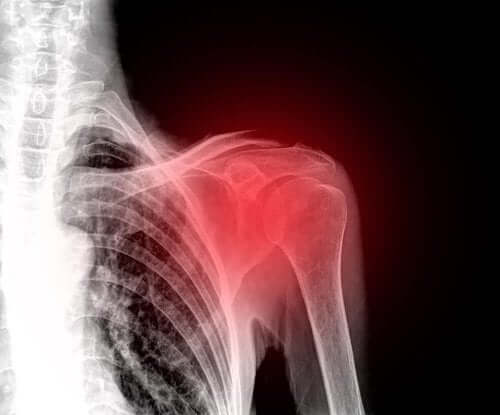

Uszkodzenie stożka rotatorów: co warto wiedzieć?

Uszkodzenie stożka rotatorów wywołuje ból i ogranicza ruchy ramienia. W poniższym artykule wyjaśnimy, na czym polega ten uraz i dlaczego do niego dochodzi.

Uszkodzenie stożka rotatorów to częsty uraz, który dotyka ramiona osób w średnim wieku. Tym samym to jedna z głównych przyczyn bólu ramienia.

Na samym początku lekarz przeprowadzi badanie, aby zdiagnozować uszkodzenie stożka rotatorów. W tym celu sprawdzi możliwość poruszania ramieniem oraz przekona się, czy występuje ból stawu.

Poza tym w celach diagnozy często wykorzystuje się dodatkowe badania, takie jak badanie ultrasonograficzne lub rezonans magnetyczny. USG pozwala lekarzowi ocenić stan ścięgien i mięśni podczas ruchu. Poza tym to powszechnie dostępne i mało inwazyjne metody diagnostyczne.